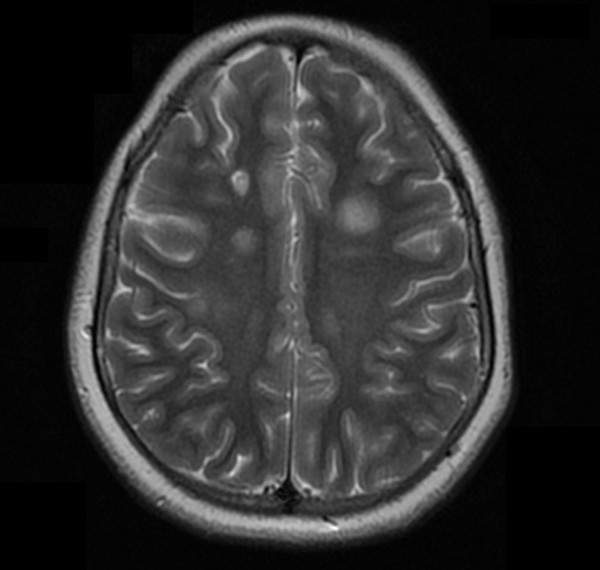

Cinco meses después del inicio de la clínica se solicita de manera ambulatoria una nueva resonancia craneomedular.

En comparación con el estudio previo, han aparecido nuevas lesiones a nivel infratentorial, tanto en el bulbo como en la protuberancia y el mesencéfalo.

La disposición de las lesiones es muy sugestiva de enfermedad desmielinizante y se cumplen criterios de diseminación en espacio y tiempo de esclerosis múltiple con signos de actividad y progresión.